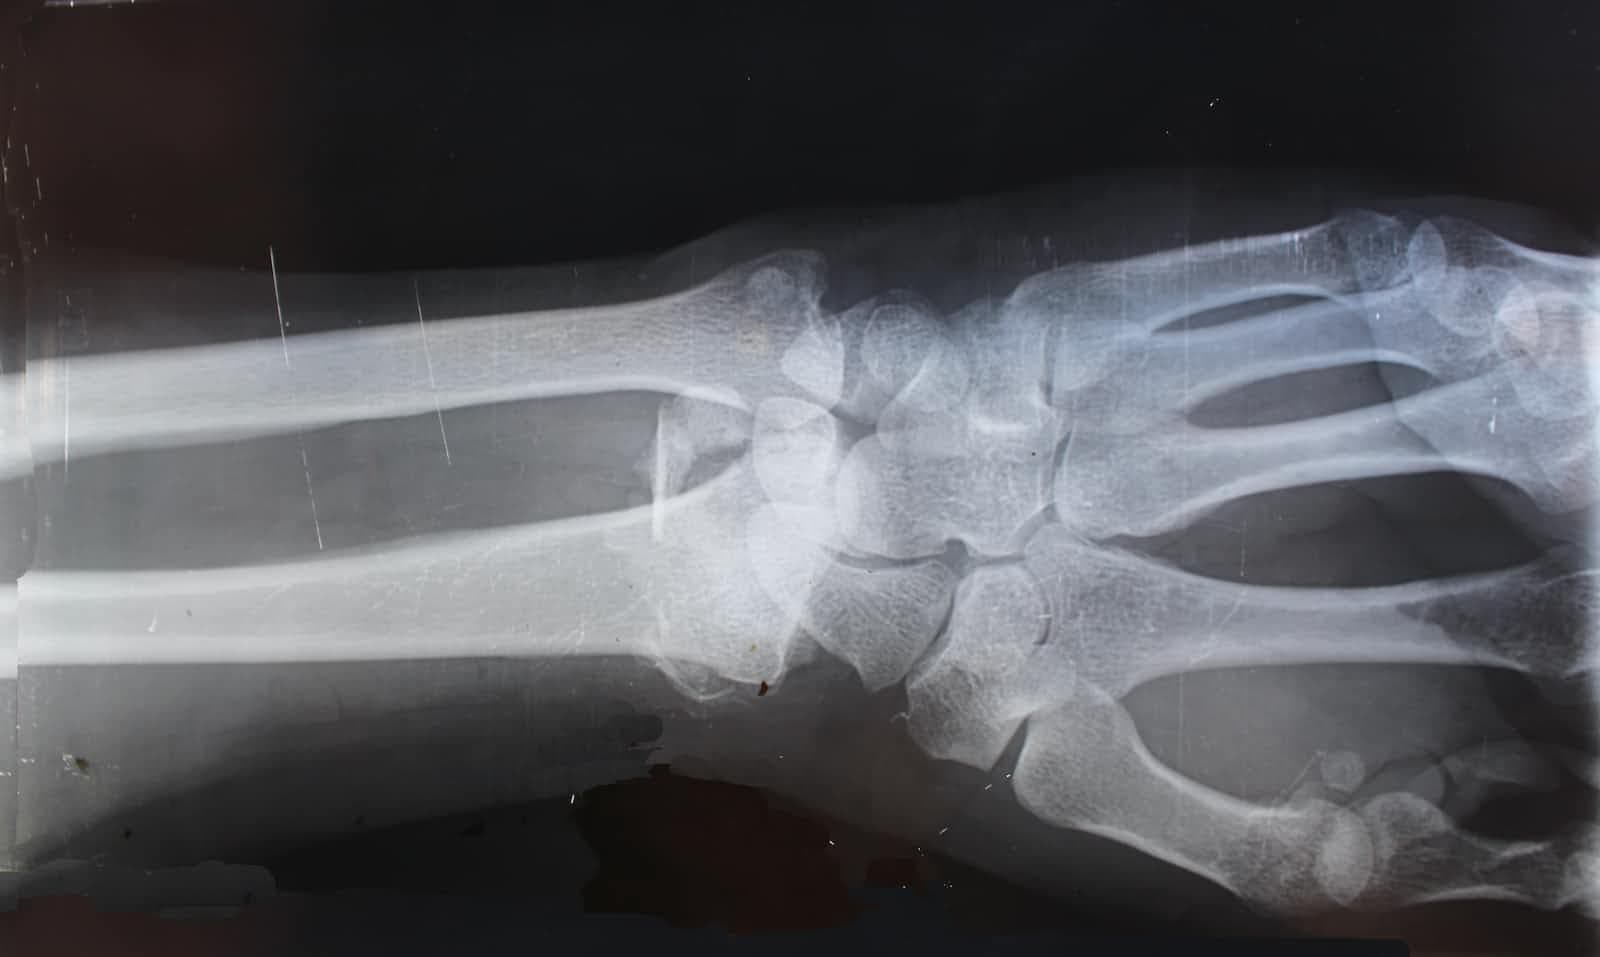

A relative of mine had an accident. He got knocked down by a bus while he was waiting to cross the road and fractured his wrist.

Being afraid of expensive treatment, he went to a traditional medicine man who helped set it back but left it misaligned....